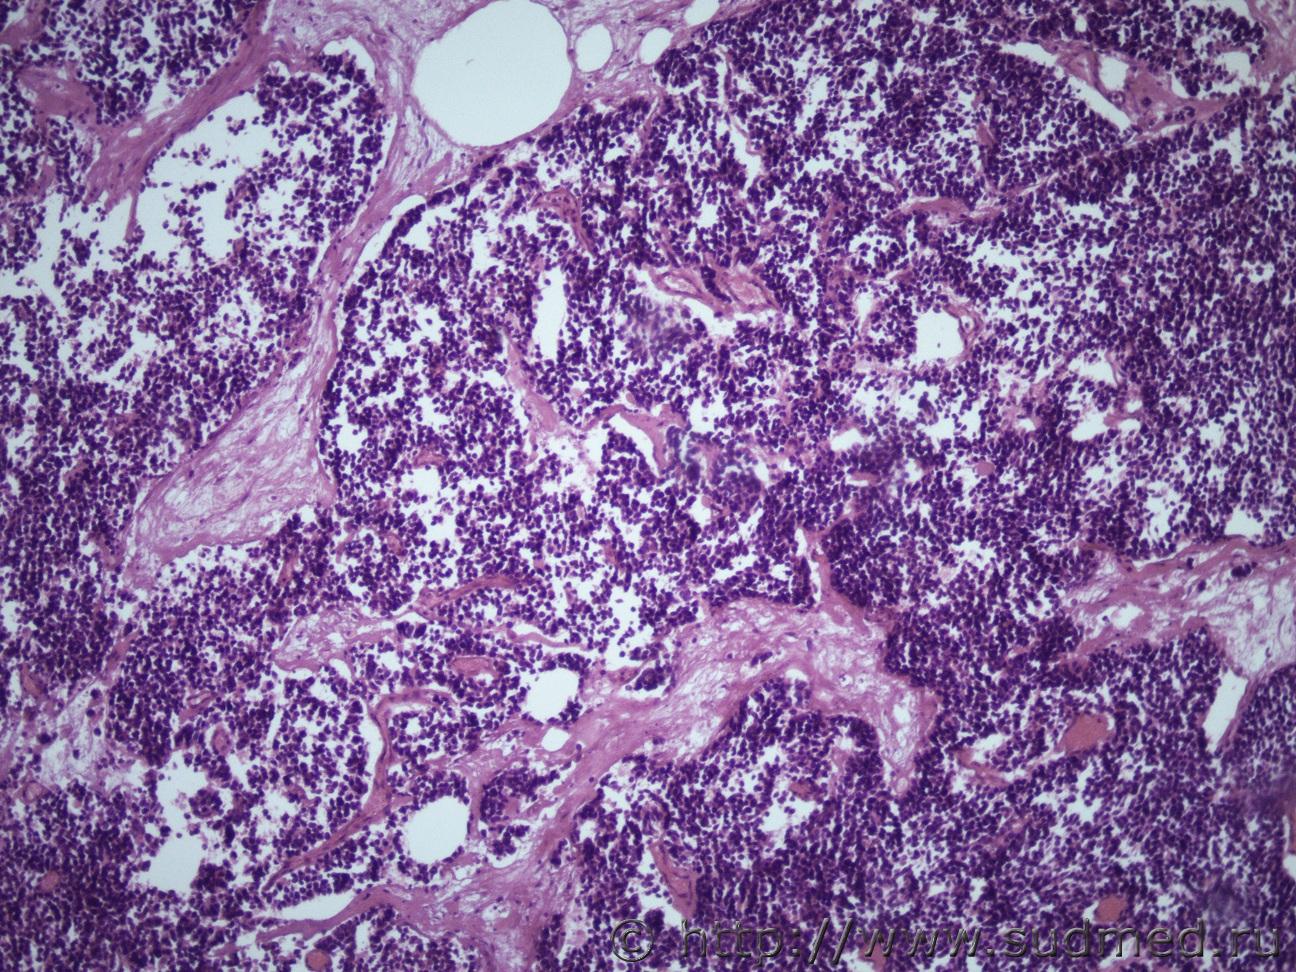

Ув. коллеги и снова здравствуйте. Как всегда опухоль. Макро- опухоль поджелудочной железы с прорастанием в окружающую клетчатку с метастазами в перибронхиальные, перипортальные ЛУ, в прикорневые отделы легких, в стенку желчного пузыря, тонкого кишечника. Легкие Судебная медицина - Прикрепленное изображение Судебная медицина - Прикрепленное изображениеСудебная медицина - Прикрепленное изображениеСудебная медицина - Прикрепленное изображение, перибрЛУСудебная медицина - Прикрепленное изображение ПЖ Судебная медицина - Прикрепленное изображениеСудебная медицина - Прикрепленное изображение , печеньСудебная медицина - Прикрепленное изображение Судебная медицина - Прикрепленное изображение Судебная медицина - Прикрепленное изображение Судебная медицина - Прикрепленное изображение Судебная медицина - Прикрепленное изображение, тонк кишСудебная медицина - Прикрепленное изображение

Наиболее подходит нейроэндокринный рак

Спасибо, рассмотрю этот вариант. Я все думала может НД протоковая аденокарцинома или мелкоклеточный рак.

Солидарен.

Непохоже.